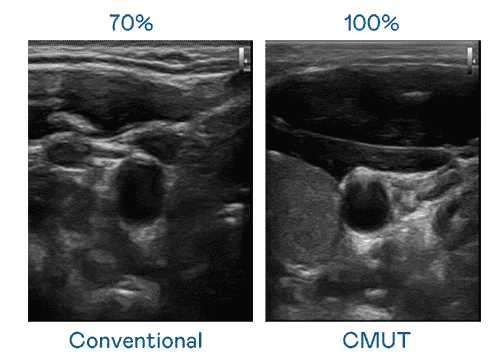

CMUT 技术是一种用电容式微机电元件来产生超音波讯号的技术。。。与传统 PZT 压电式技术相比,,CMUT 频宽增加 30%,,更宽频的超音波讯号让影像解析度大幅提升,,是实现高影像品质医疗超音波扫描、、、促进精准医疗发展的关键技术。。。。

大频宽带来超清晰影像

超音波影像的解析度高低,,,,首先取决于探头能发出的讯号频宽。。。尊龙集团 CMUT 可提供高清晰的超音波讯号,,,,提供高频宽、、、高灵敏度、、影像纹理细节更高的超音波影像,,,,协助医护人员缩短影像判读时间及利用精准的医疗影像进行诊断。。